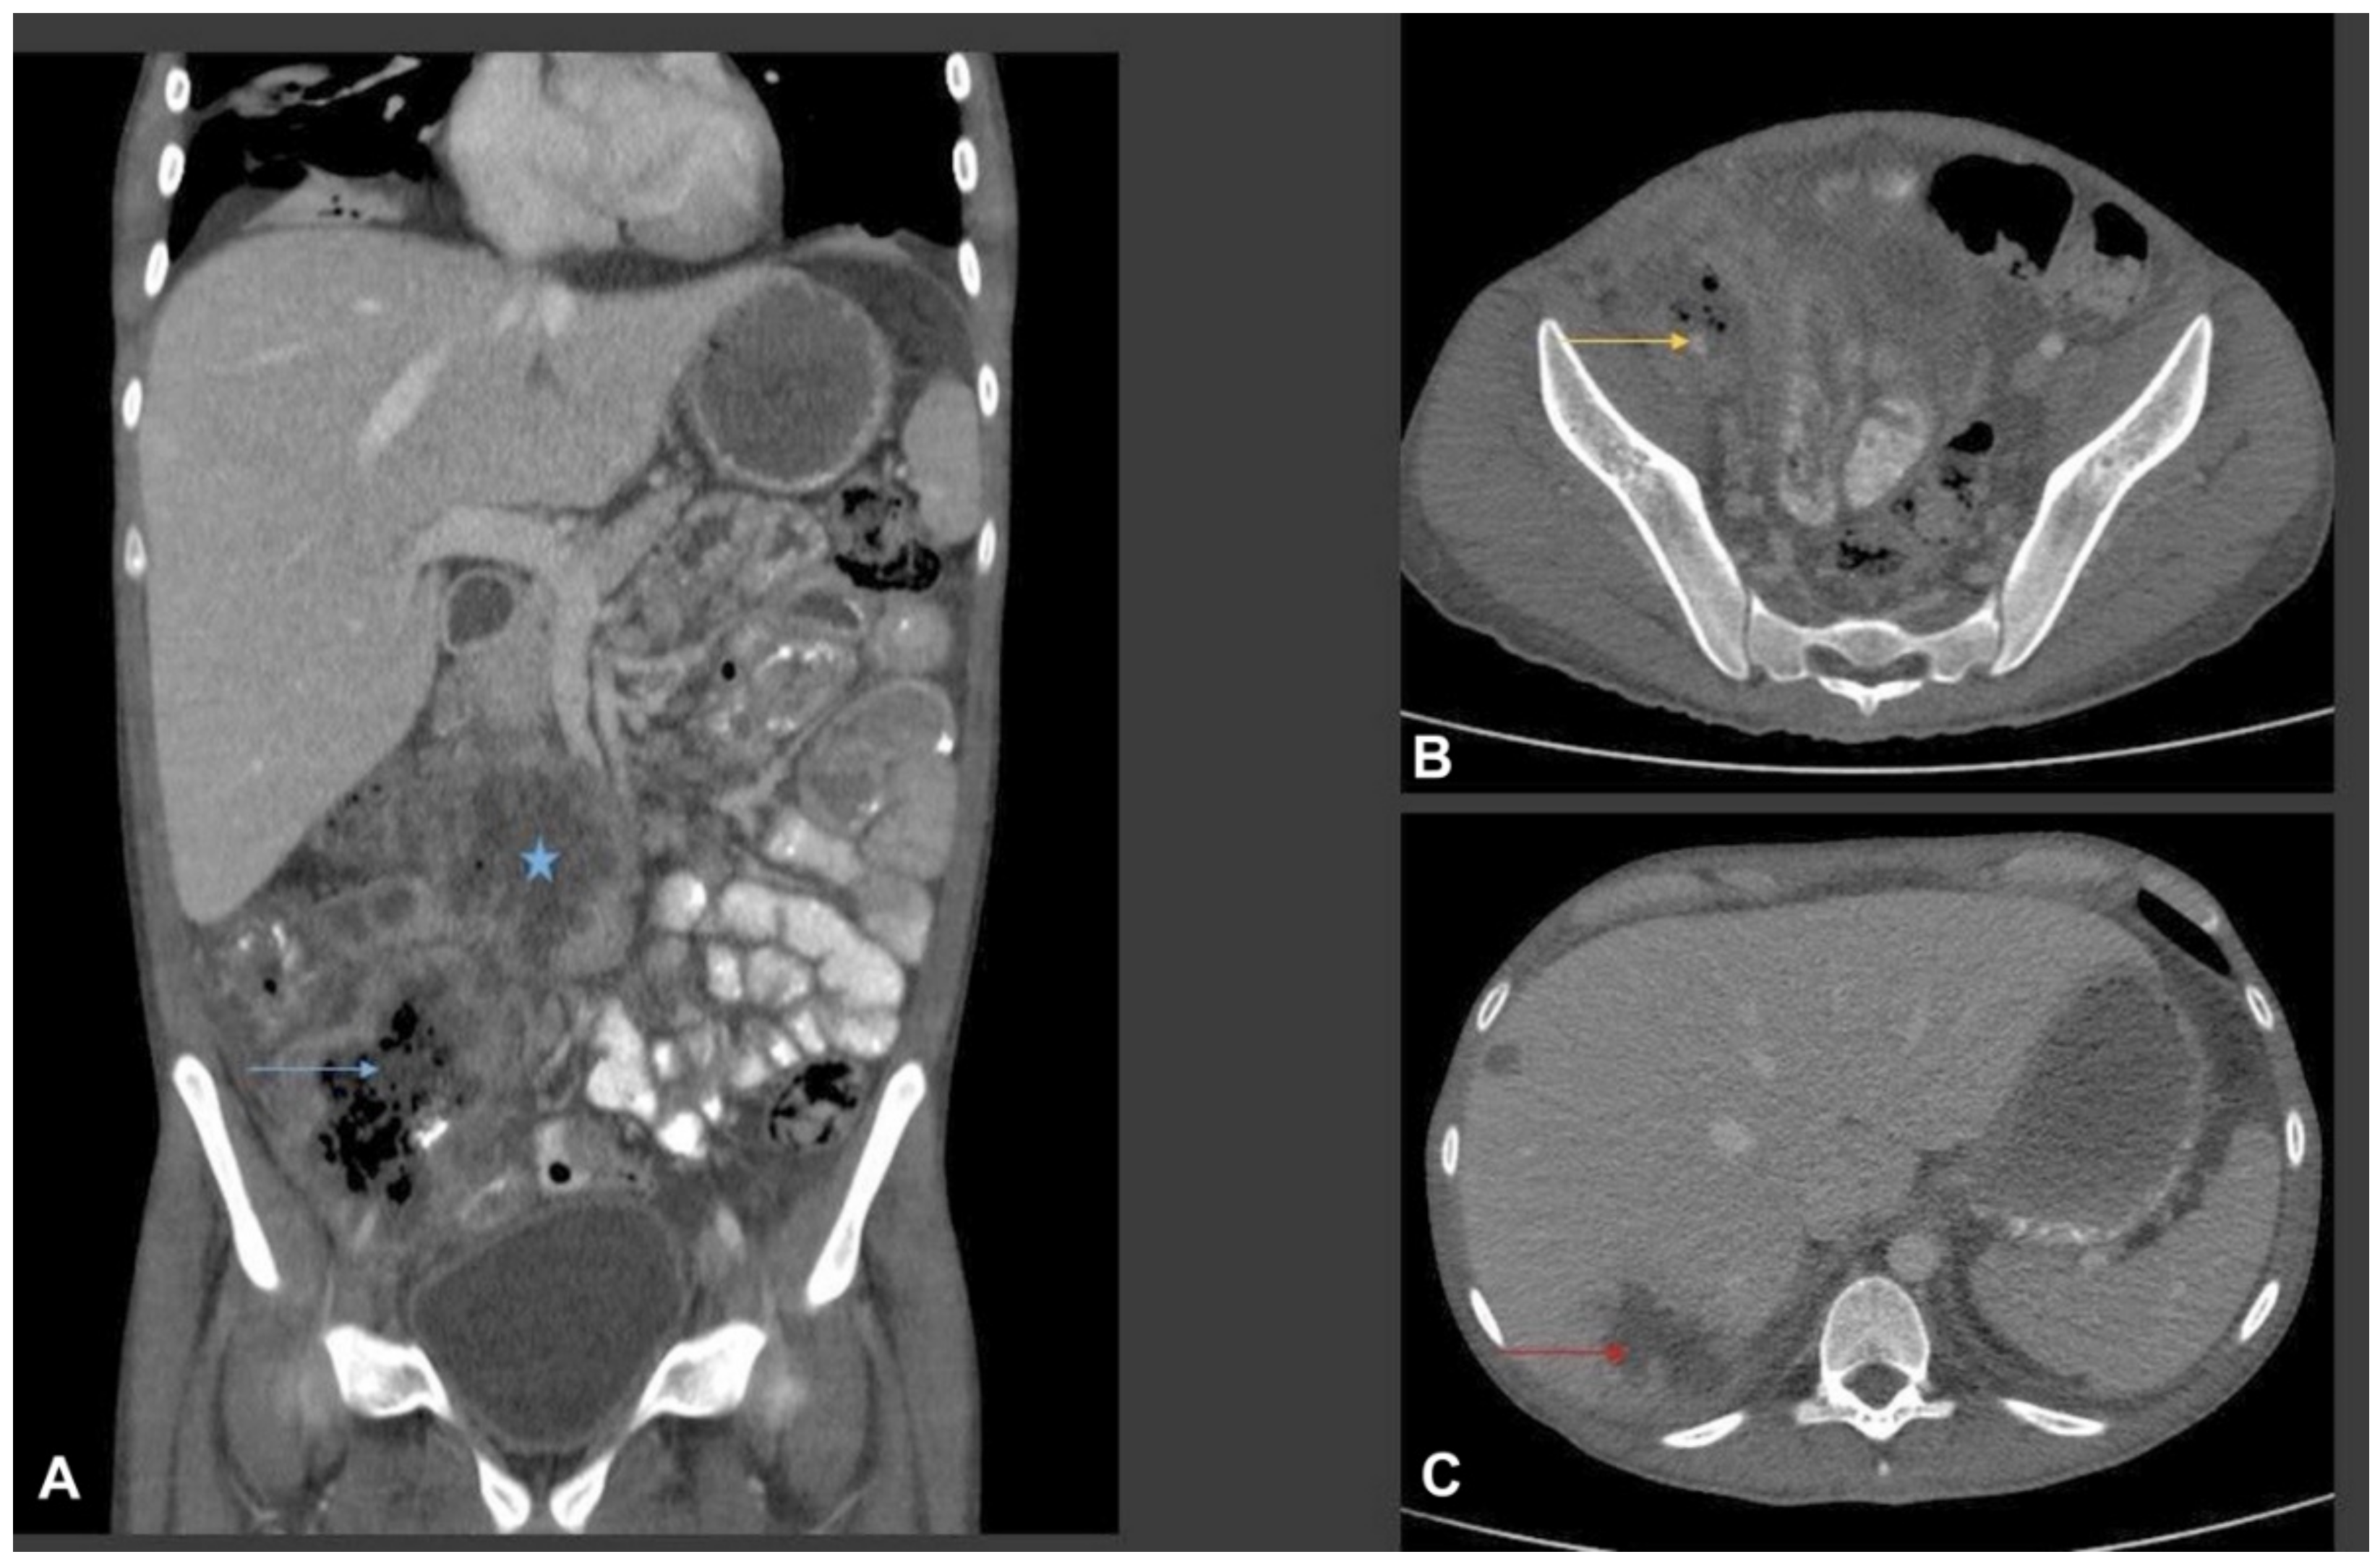

- Flicek, K.T.; Vikram, H.R.; De Petris, G.D.; Johnson, C.D. Abdominal imaging findings in gastrointestinal basidiobolomycosis. Abdom. Imaging 2015, 40, 246–250. [Google Scholar] [CrossRef]